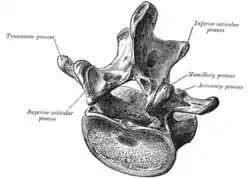

In anatomy, a process (Latin: processus) is a projection or outgrowth of tissue from a larger body.[1] For instance, in a vertebra, a process may serve for muscle attachment and leverage (as in the case of the transverse and spinous processes), or to fit (forming a synovial joint), with another vertebra (as in the case of the articular processes).[2] The word is also used at the microanatomic level, where cells can have processes such as cilia or pedicels. Depending on the tissue, processes may also be called by other terms, such as apophysis, tubercle, or protuberance.

- The spinous, articular, transverse, accessory, uncinate, and mammillary processes of the vertebrae